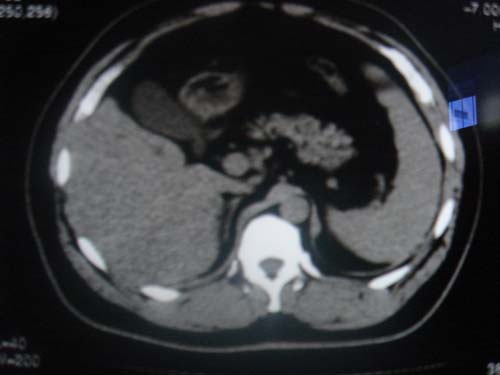

患者 男 40 右上腹不适 有胆囊息肉病史2年

本例就是胆囊比较大,内密度不很均匀,疑有砂砾状结石,未见息肉以及其他异常。

肝脏增大,

片中示肝脏的ct值低于脾脏,肝脏右叶外缘部份凹凸不平,考虑脂肪肝,肝硬化可能。结合其检查如b超或ct增强检查。

胆内胆管结石,第十二幅肝内似类圆形等密度灶.强化后再说吧或者做其它检查.

胆囊未见明显异常,肝脏密度似比脾脏密度低,测量一下ct值排除一下脂肪肝.当然做一下增强或mr就更好了.

肝右叶密度不均,脾大。强烈要求增强扫描除外浸润型肝癌。

肝大   密度降低  脾大  脂肪肝?